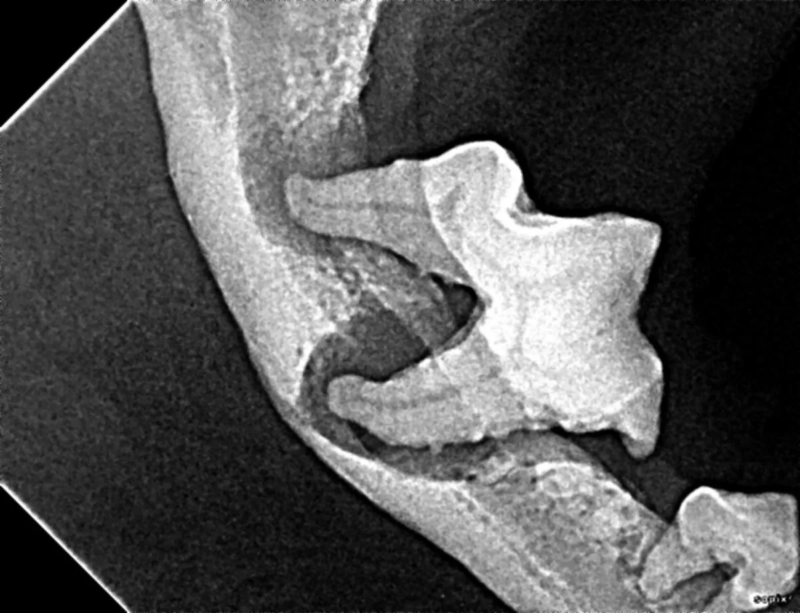

The Center now provides advanced imaging via cone beam CT. Cone beam CT is excellent for visualization of bony structures of the skull, nasal cavity, teeth, and ears. Cone beam CT is especially helpful for diagnosing dental disease and evaluation of jaw fractures. It can also be useful for evaluating the sinuses and tympanic bulla. Cone beam CT can be used in conjunction with nasal biopsy and culture to evaluate nasal discharge whether chronic or acute.

Pets can be involved in trauma that can cause fractures to their head, teeth, and jaw bones. Correctly repairing these fractures is extremely important for your pet to have normal function of their mouth. If a jaw fracture is allowed to heal in an abnormal position, your pet may have great difficulty chewing and can be in significant pain. Many fractures can be successfully treated with minimally invasive oral procedures, but more complicated cases may require bone plating techniques. The Center offers cone beam CT imaging which provides extremely detailed images of the bones of the head and skull. Advanced imaging with CBCT facilitates selection of the best surgical technique to get your pet back to eating and comfort as soon as possible.